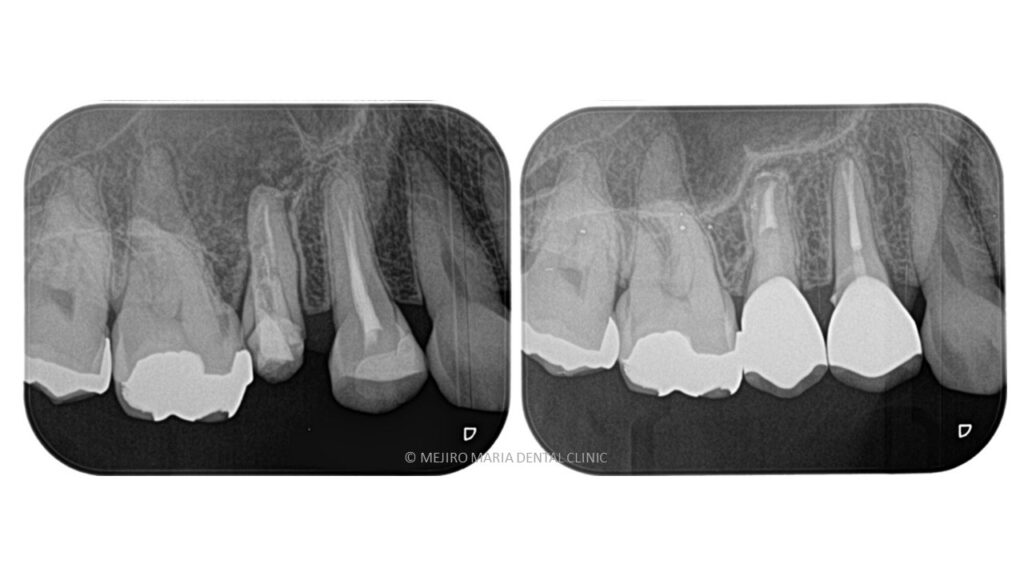

【症例】再根管治療| CT、マイクロスコープを使った精密根管治療

治療内容 再根管治療|精密根管治療

治療期間 1週間

治療回数 2回

治療費用 154,000円(税込)

※処置当時の料金